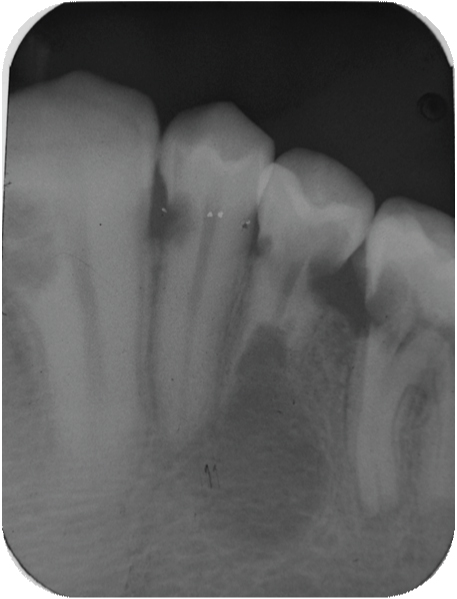

[Table/Fig-3] showing the normal morphology of crowns of the maxillary teeth. [Table/Fig-4] showing the normal morphology of crowns of the mandibular teeth. Full mouth intraoral periapical radiograph revealed complete root resorption in relation to 11, 12, 41 and 42; cervical resorption in 15, 33, 34 and 43, 44; apical resorption in 16, 24, 25 and 26. Resorption in both apical and cervical region was noticed in relation to 35, 36 and 46. Panoramic radiographs showed multiple ill defined radiolucent areas in apical third and cervical region of all teeth in varying degree. Lateral view of skull showed no evidence of any skull changes. In [Table/Fig-5] intraoral periapical radiograph showing complete root resorption in relation to 11 and 12. In [Table/Fig-6] intraoral periapical radiograph showing complete root resorption in relation to 41 and 42. In [Table/Fig-7] intraoral periapical radiograph showing cervical resorbtion in relation to 15 and apical root resorption of mesial and distal roots in relation to 16. Loss of PDL space in 17 can be appreciated.

Intraoral periapical radiograph showing cervical resorbtion in relation to 15 and apical root resorption of mesial and distal roots in relation to 16. Loss of PDL space in 17 can be appreciated

The common complaint of the patient with idiopathic root resorption is mobility of the involved tooth. Therefore this condition can be confirmed only by radiograph. Patient had class II malocclusion with increased overjet and overbite but compensatory thickening of cementum layer increased periodontal space could not be appreciated ruling out occlusal stress to be the aetilogical factor. ([Table/Fig-7] shows cervical resorption in relation to 15 and apical root resorption of mesial and distal roots in relation to 16, there is loss of PDL space in 17). All teeth had vital pulps and there was no periodontal or periapical inflammation. By definition, idiopathic external root resorption is a diagnosis of exclusion. Hence, in the absence of any plausible causative factor we considered this case as multiple idiopathic apical root resorption.